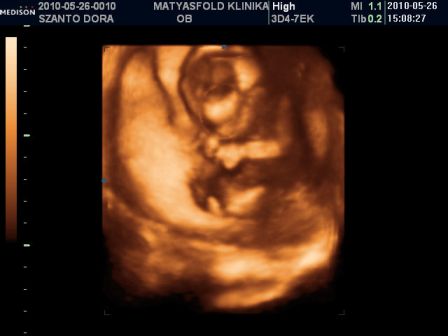

Itt a kezecskéjét és az öklét látni...

Kép

Pussz: Tigrisék

A végén pedig a hátát mutatta nekünk, mintha azt mondaná: Na ennyi elég volt mára, szeretnék pihenni!